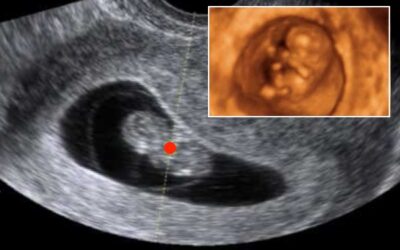

Presentaron un proyecto de ley del latido cardíaco fetal

Una numerosa concurrencia acompañó la presentación en dependencias del Congreso de un proyecto de “ley del latido”, que restringe el aborto a partir de detectarse el latido del corazón.